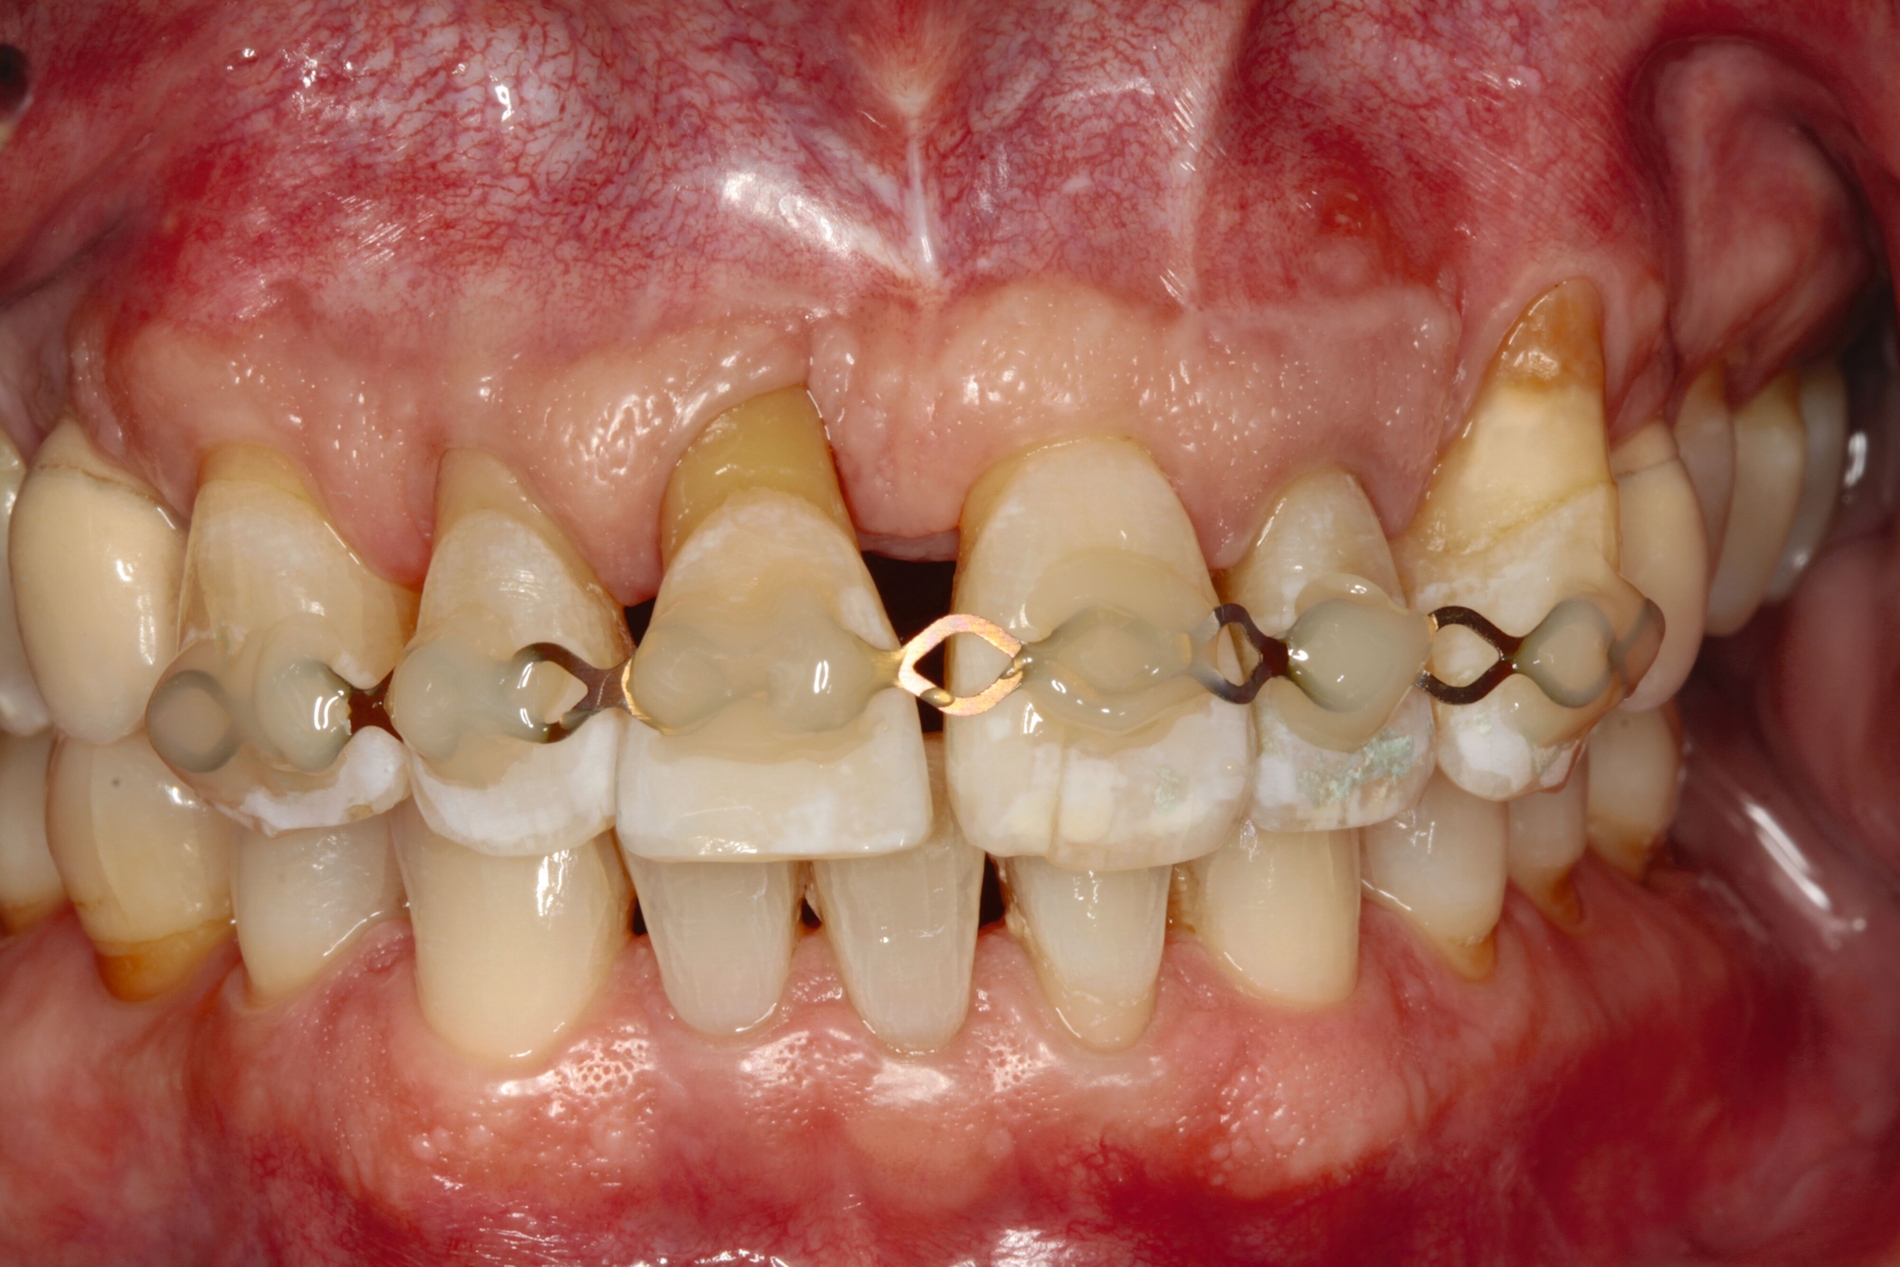

Entsprechend der hier aufgeführten schwachen wissenschaftlichen Evidenz lässt sich schlussfolgern, dass Zähne mit einem Lockerungsgrad II oder höher möglicherweise von einer Schienung vor regenerativen parodontalchirurgischen Eingriffen profitieren können [Cortellini et al., 2001]. Diskutiert wird in diesem Zusammenhang die Förderung der Stabilität des Blutkoagulums durch die Reduktion der Mobilität der Zähne in der Heilungszeit. Nicht zuletzt kann durch eine Schienung das aufgrund der Mobilität mögliche sekundäre okklusale Trauma reduziert beziehungsweise eliminiert werden. In diese Schienungen wird in der Regel jeweils ein benachbarter Zahn ohne erhöhte Mobilität einbezogen. Zwei verschiedene Schienungen zur Reduktion der Mobilität im Rahmen der regenerativen Parodontalchirurgie sind in den Abbildungen 3 und 4 dargestellt.